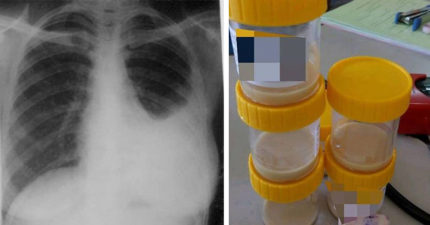

24歲男抽菸7年,拿針刺肺「流出超濃稠黃液」!清完5罐還是慘死。